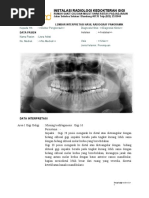

9. Pasien perempuan datang dengan keluhan nyeri pada r

ahang bawah sebelah kiri. Pasien telah melakukan foto pa C.Pulpitis

noramik. Apakah diagnosis dari gambar di samping menu D.Pericoronitis

rut klasifikasi impaksi pell and gregory?

a. Klas IB mesioangular

b. Klas IIB vertikal

15. Seorang pasien perempuan usia 20 tahun datang ke

c. Klas IA horizontal dokter gigi karena ada gigi depannya yang tidak tumbuh.

d. Klas IIIC horizontal Pada pemeriksan klinis yang ditunjang foto panoramik

terdapat impaksi pada gigi 13. Dokter gigi memutuskan

e. Klas IIC vertikal perawatan untuk menegeluarkan gigi tersebut dengan

9. Pasien perempuan datang dengan keluhan nyeri pada

sebagian untuk ukuran mesio-distal mahkota gigi molar

rahang bawah sebelah kiri. Pasien telah melakukan foto

tiga yang impaksi, dan puncak tertinggi molar ketiga

panoramik. Apakah diagnosis dari gambar di bawah ini

berada dibawah servikal molar kedua. Apakah Klassifikasi

menurut klasifikasi impaksi pell and gregory?

B. Klas IIB vertikal A. Operkulektomi

C. Klas IA horizontal B. Odontektomi

D. Klas IIIC horizontal C. Alveolektomi

E. Klas IIC vertical D. Bedah flap